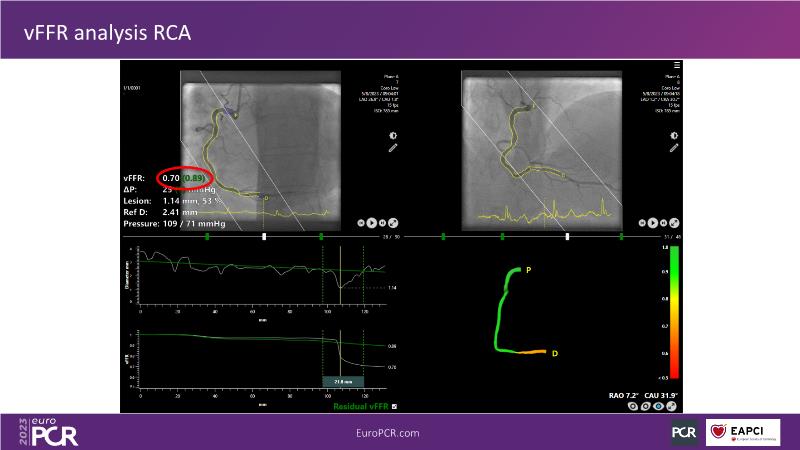

Explore angiography-based FFR/virtual FFR in this session. Uncover clinical evidence, identify ideal patients, and learn step-by-step integration into daily practice.

• To know the clinical evidence behind angiography-based FFR/vFFR

• To learn step by step how to apply it in your daily practice